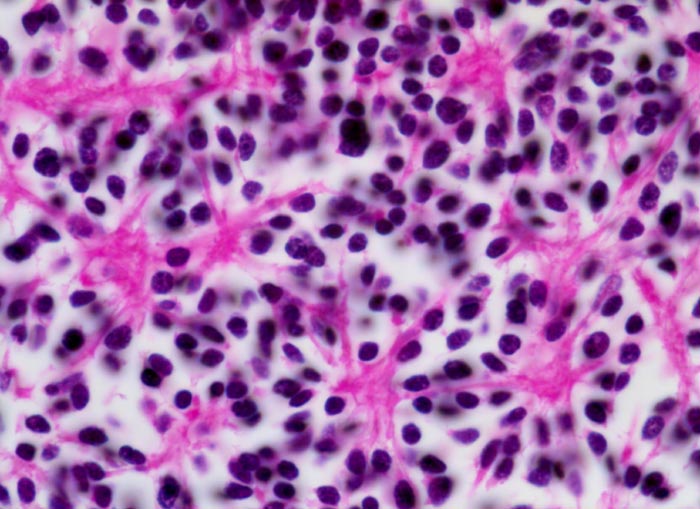

Wegen der hohen Zelldichte und der hohen Kern-Zytoplasmarelation erscheinen die Tumoren in der HE Färbung blau. Medulloblastome müssen differentialdiagnostisch von morphologisch ähnlichen kleinzelligen undifferenzierten Karzinomen und Lymphomen abgegrenzt werden. Das klassische Medulloblastom besteht aus dicht gepackten Zellen mit runden bis ovalen oder karottenförmigen stark hyperchromatischen Kernen umgeben von wenig Zytoplasma. Runde Zellen mit weniger dichtem Chromatin sind oft beigemischt. Zahlreiche Mitosen, flächenhafte Nekrosen und Apoptosen sind typisch. In weniger als einem Drittel der Fälle findet man die typischen Homer-Wright Rosetten. Diese bestehen aus ringförmig angeordneten Tumorzellkernen um ein fibrilläres Zentrum aus Zytoplasmafortsätzen.

• Scharf begrenzter rundlicher sehr zellreicher (deshalb blauer) Tumor.

• Monomorpher Zellrasen mit hyperchromatischen ovalen oder karottenförmigen Zellkernen.

• Kaum erkennbares Zytoplasma.

• Homer-Wright Rosetten aus ringförmig angeordneten Tumorzellkernen um ein fibrilläres Zentrum aus Zytoplasmafortsätzen.